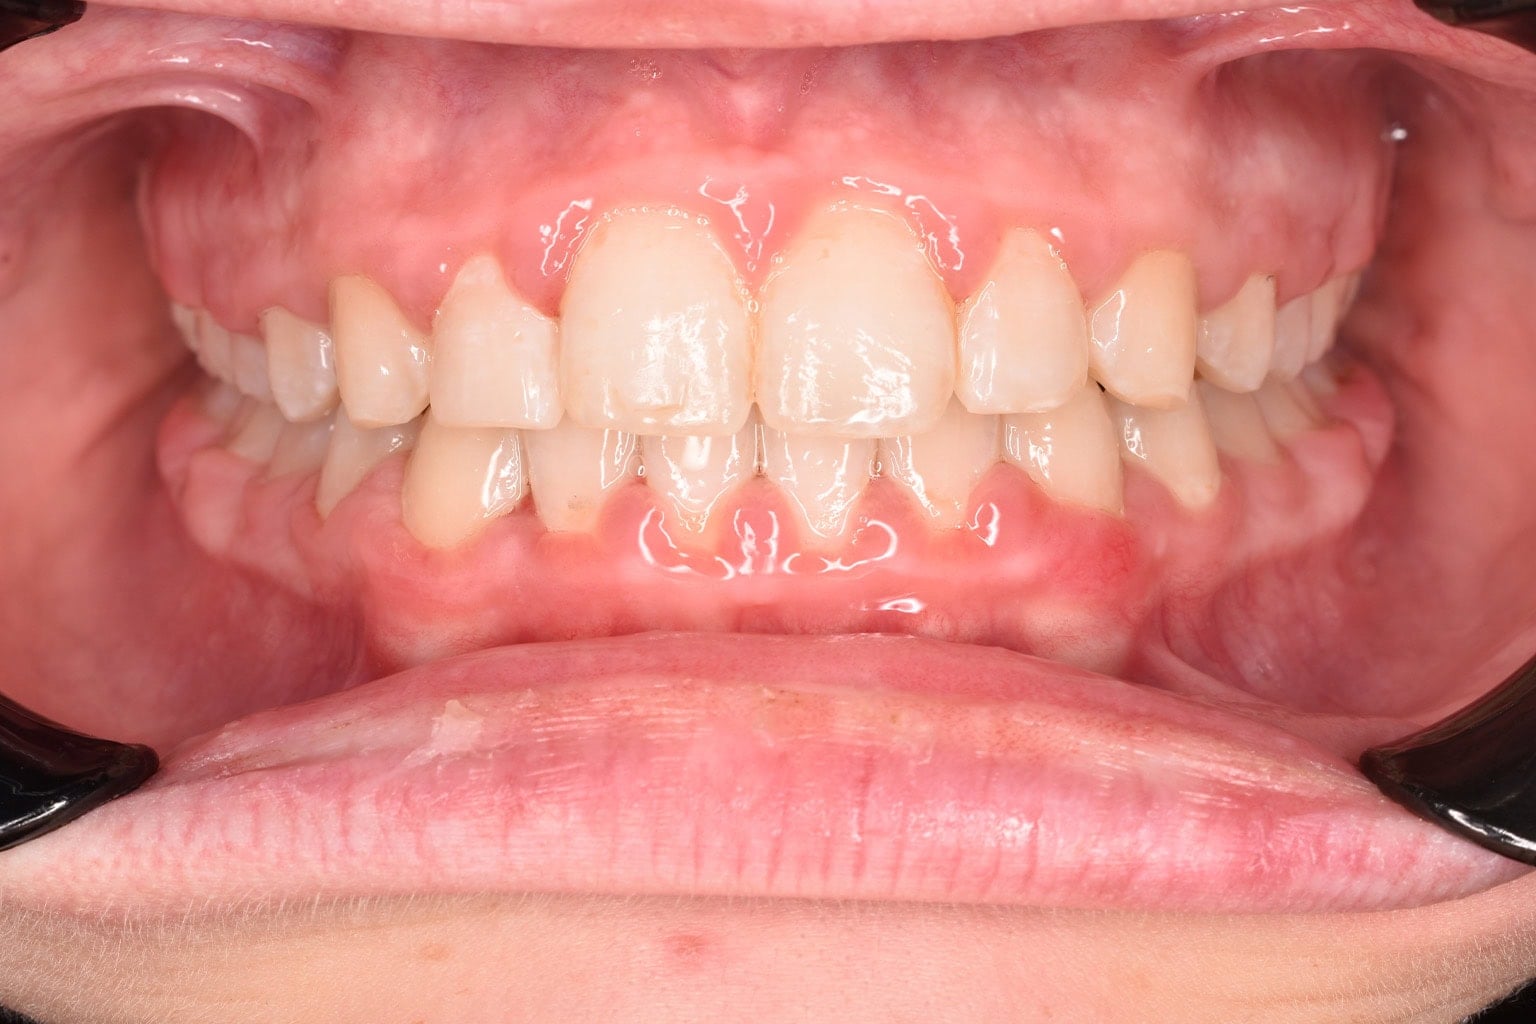

Vorher-Nachher-Ergebnisse

Echte Ergebnisse. Echte Menschen.

Jede Behandlung bei TIEFBLAU Kieferorthopädie ist so individuell wie der Mensch dahinter. In unserer Vorher-Nachher-Galerie zeigen wir Ihnen echte Behandlungsergebnisse aus unserer Praxis in der Kölner Südstadt: Schonend erzielt, präzise geplant und mit dem Anspruch, den wir seit über 40 Jahren an jede Behandlung stellen.

Die Bilder geben Ihnen einen Eindruck davon, was moderne Kieferorthopädie leisten kann, ob bei Kindern, Jugendlichen oder Erwachsenen.

Der sichtbare Unterschied

Dokumentiert. Überzeugend. Nachhaltig.